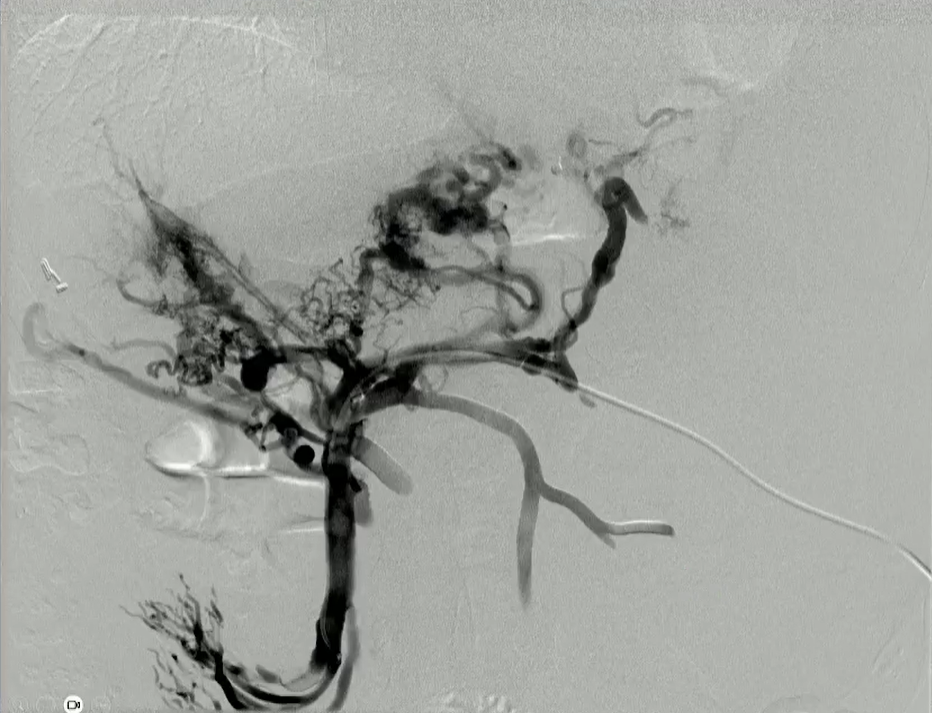

结果:术后影像学检查显示门静脉和脾静脉的血流情况有所改善,且残留血栓极少。

通过经颈静脉肝内门体分流术(TIPS)治疗慢性门静脉血栓时所涉及的技术复杂性和决策难题,尤其是在标准方法因血栓程度过重而无法实施的情况下更是如此。 采用脾经脏穿刺术治疗门静脉高压症的方法证明能够有效克服这些难题,从而成功实施了经颈静脉肝内门体分流术(TIPS)。 PVR-TIPS 作为一线治疗方案:PVR-TIPS 为慢性门静脉血栓的治疗提供了一种技术上可行的解决方案,克服了标准 TIPS 安装所面临的难题。 持久效果:该干预措施不仅恢复了门静脉的血流,而且在后续随访中还显示出持续的通畅性以及血栓的完全消散。